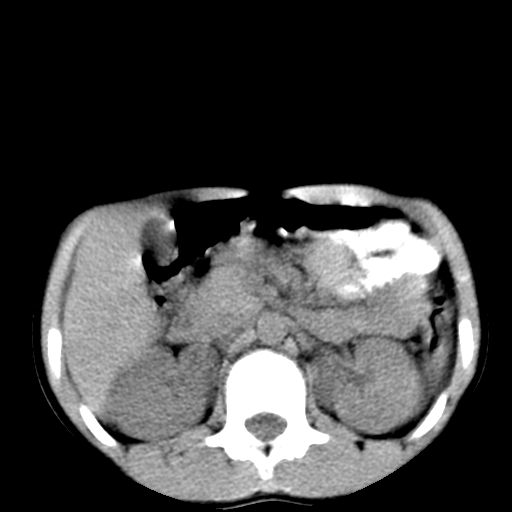

腹部好象未见异常。

腹部ct平扫未见明确异常

腹部ct平扫不能提示哪里有病变。